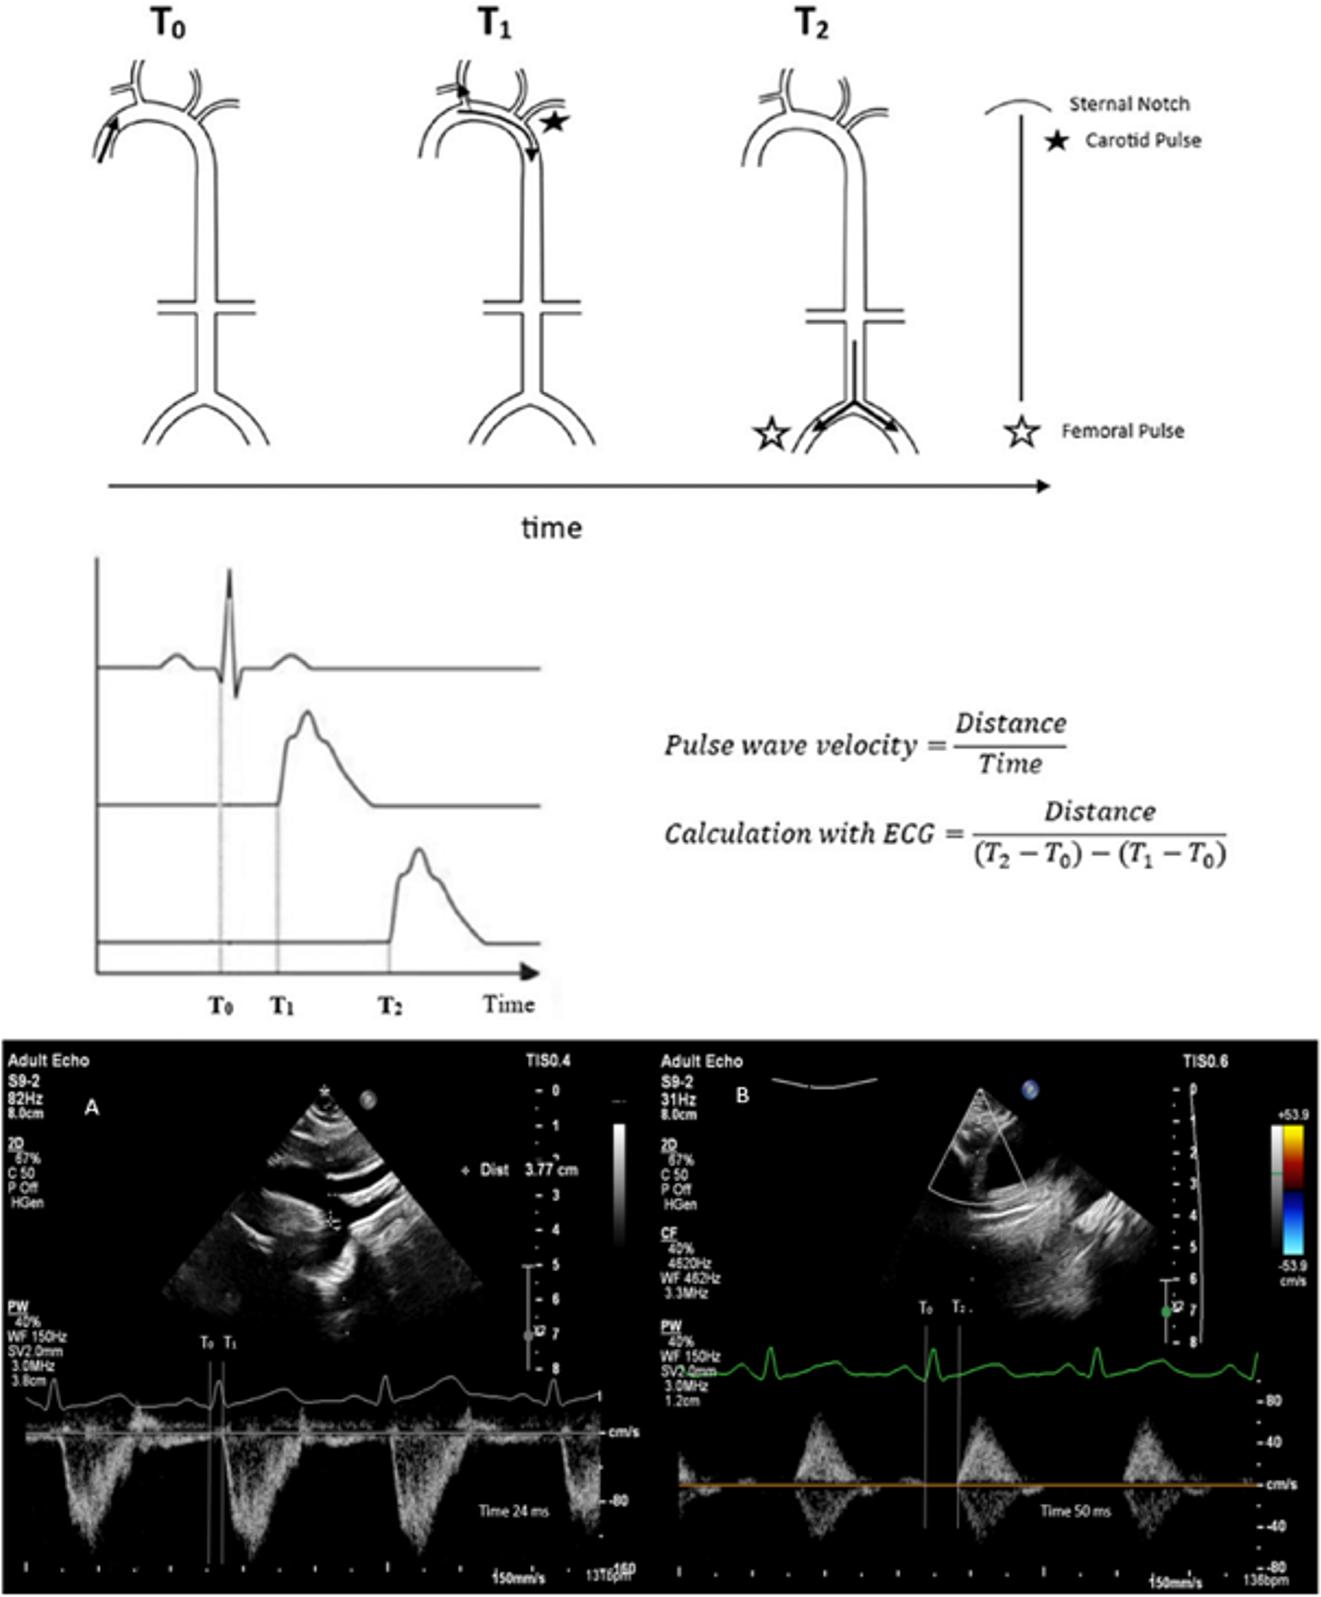

PWV measurements were performed between 14.00 and 17.00 hours in a temperature-controlled room using the same device. Measurements were taken when infants were at their calmest, with calculations performed three times. The calculation involved taking pulse waves and simultaneous ECG images from the sternal notch and femoral artery. The pulse wave was measured on the descending aorta from the sternal notch, and the distance from notch to measurement site was calculated. Then, the femoral artery pulse wave was measured, and the distance between sternal notch and femoral artery measurement site was measured. The distance (d) was calculated by subtracting the sternal notch-to-aorta distance from the sternal notch-to-femoral artery distance. The time to pulse wave onset was calculated from the QRS waves on ECG. The carotid-femoral pulse wave velocity (cfPWV) was obtained by dividing distance (d) by the difference between the QRS-to-femoral and QRS-to-aorta pulse wave times (Fig. 1).